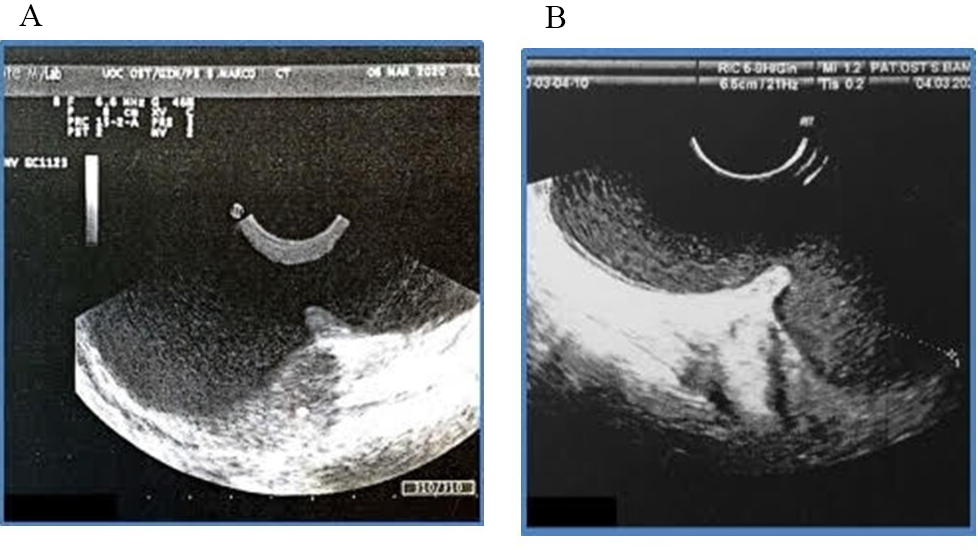

Perineal ultrasound (Fig. 1) was performed and showed evidence of two very large masses connected by a narrow neck of 10.6 cm in longitudinal diameter, configuring an unusual dumb-bell shaped presentation of Bartholin’s gland cyst. Cross fluctuation between them was noted.

Fig. 1.Perineal Ultrasound scan with dumb-bell shape of the bilobar Bartholin’s cyst. (A) Perineal ultrasound of dumb-bell shape. (B) Longitudinal diameter of the bilobar Bartholin’s gland cyst.